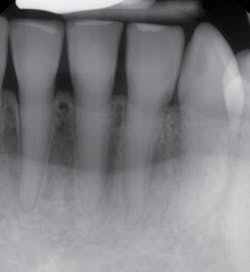

Radiographs—The teeth exhibit pulpal-root canal obliteration (see Figures 4, 5). The roots of the teeth are narrow and appear to be funnel-shaped. The crowns are large and there is constriction at the cervical neck of the tooth.